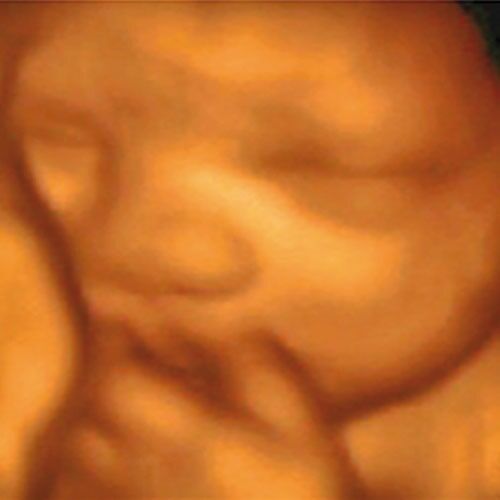

2. Un estudio 3D y 4D mostrando expresiones de la cara de su bebé👶 como lo son gestos o sonrisas 😃

3D son fotos impresas de la carita de su bebé.

4D Son los movimientos de su bebé en tiempo real .